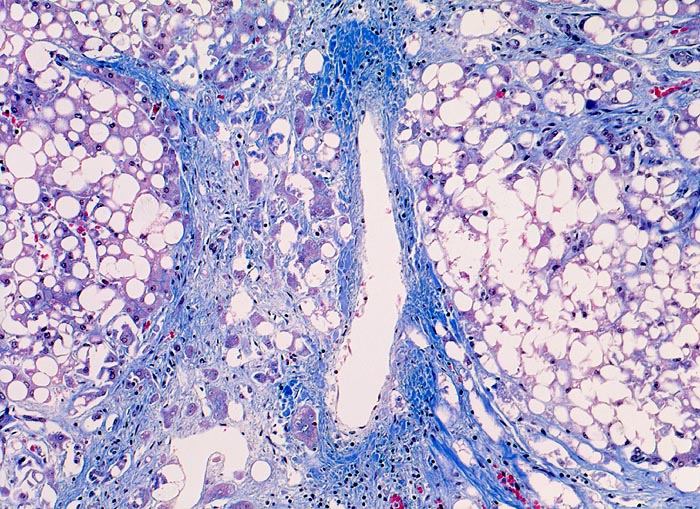

Parenchymknoten ( Pseudolobuli) 1-2 mm im Durchmesser sind von (blauen) Bindegewebsringen umgeben. Die Knoten sind monolobulär, d.h. ohne Zentralvenen oder Portalfelder. Die ursprünglichen Zentralvenen und Portalfelder sind eingemauert in das stark vermehrte, ringförmig angeordnete Bindegewebe. Das knotige Parenchym ist diffus grobtropfig verfettet. Schon in der Übersicht sind Mallory Körper erkennbar.

Die ausgeprägte Steatose weist auf einen aktuell bestehenden Alkoholabusus hin. Die breiten Bindegewebssepten sind typisch für die aethylisch bedingte Zirrhose.